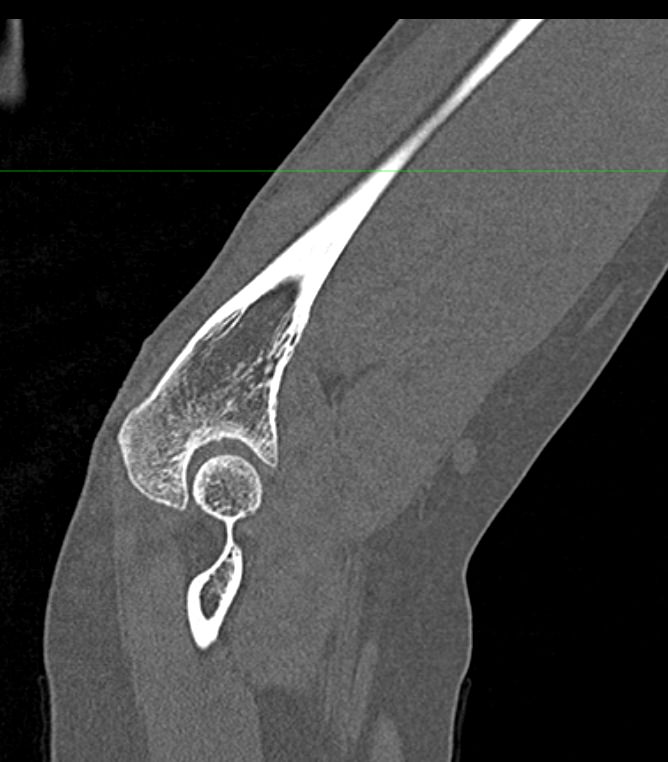

Одним из наиболее информативных методов исследования локтевого сустава является мультиспиральная компьютерная томография. Мультиспиральная КТ локтевого сустава позволяет оценить состояние костных структур и капсульно-связочного аппарата сустава. В отличие от обычного рентгена, при котором изображения накладываются друг на друга, мультиспиральная компьютерная томография с помощью рентгеновских лучей сканирует исследуемую область в разных плоскостях, делая множество тончайших срезов и преобразуя данные в цифровые трехмерные изображения.

Костная ткань хорошо поглощает рентгеновские лучи, поэтому кости ярко визуализируются на снимках КТ. Компьютерная томография в первую очередь востребована в ортопедии и травматологии. Методика широко применяется для диагностики костной патологии. С помощью КТ можно оценить плотность костной ткани и выявить косвенные признаки остеопороза. В случае перелома можно определить точную локализацию костных отломков, что особенно важно при планировании оперативного вмешательства и в послеоперационном периоде для наблюдения за процессом восстановления. КТ также помогает в диагностике различных артритов и артрозов.

- Что покажет КТ локтевого сустава

Что покажет КТ локтевого сустава

- врожденные особенности строения;

- сокращение плотности костей при остеопорозе;

- воспалительные процессы не только в самом суставе, но и в тканях, которые окружают его;

- переломы и трещины костей;

- дегенеративно-дистрофические изменения;

- гнойные процессы;

- инородные тела

- новообразования костей и мягких тканей (не только первичные опухоли, но и метастазы).